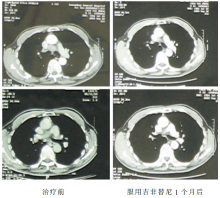

2009-09-02 胸部CT示右肺上叶肿块,大小约29×25 mm,纵隔内气管前、隆突下、肺门淋巴结肿大,最大者约21×28 mm,考虑为右上肺周围型肺癌并肺门纵隔淋巴结转移可能性大,见 图1和 图2。

2009-10-07胸部CT示右上肺肿物及肺门纵隔淋巴结较前明显缩小。